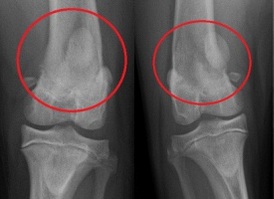

Knie     Kniescheibe ist herausgesprungen

beim Mensch     Kniescheibe ist herausgesprungen

und ist an der Seite, Röntgenfoto bei

einem Hund    Schema Knie Querschnitt

Kniescheibe ist herausgesprungen

beim Mensch

Kniescheibe ist herausgesprungen beim Mensch [4]

-- die instabile Kniescheibe [mit zu flacher Rinne] springt oft beim Sport heraus bei einer "Verdrehung des Knies" (Patella-Luxation) [web01]. Bei einer instabilen Kniescheibe reicht eine leichte Verdrehung des Knies - z.B. beim Sport - und die Kniescheibe fliegt raus [web05 (1'29''-1'36'')], oder auch bei einem Unfall kann eine instabile Kniescheibe herausspringen [web06 (20''-28''9]

-- "herausgesprungene" Kniescheiben kommen in jedem Alter vor [web04], vor allem aber bei Mädchen und jungen Frauen [web02], anatomisch begünstigt mit X-Beinen und anderen Bein-Fehlstellungen [web01]